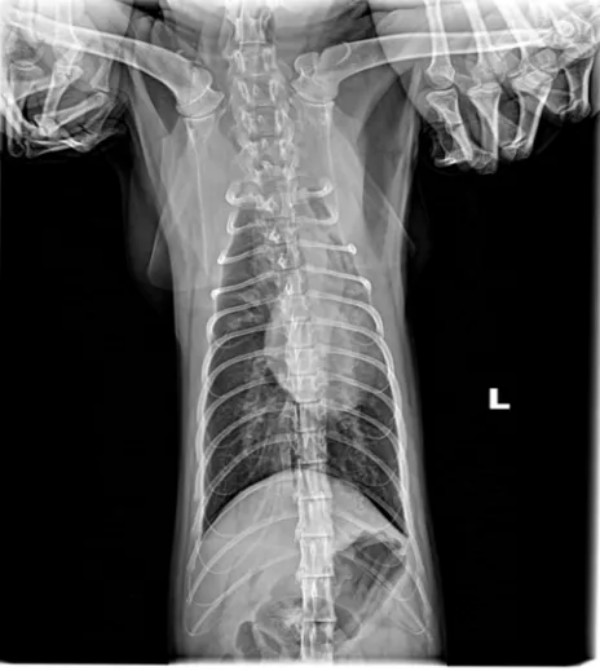

一、引言 猫咪肺炎根据发病快慢有急性肺炎和慢性肺炎之分,猫咪急性肺炎的症状主要表现为突然发高烧、呼吸不畅、腹泻等;慢性肺炎通常表现为长时间咳嗽、有痰、食欲下降、精神不振、呼吸不畅等。 猫咪如果患上肺炎就需要及时治疗,否则很容易引发相关的并发症,威胁到猫咪的性命。肺炎常见原因:感染性(细菌感染、病毒感染、寄生虫感染)、非感染性(吸入性、异物性、过敏性、继发性等) 二、病例基本信息及病史 2.1基本信息 一只缅因猫,雄性未绝育,体重5.85Kg,免疫不全,驱虫正常。 2.2主诉疾病史 最近几天精神良好,就诊当天发蔫,食欲不振,偶尔咳嗽,打喷嚏,4天前家里新领养一只小猫。既往病史 :疱疹病毒,杯状病毒,伯氏杆菌。 三、检查及化验项目和结果 3.1血常规检查 3.2 血清样淀粉蛋白检查 3.3生化检查 3.4fNT-PrOBNP猫N端脑钠肽前体 3.5影像学检查 四、诊断结果 肺炎;肺叶实变 五、治疗方案及预后 5.1经验性治疗 克维舒:一天两次,一次2ml; PO 麻杏石甘汤:一天两次,一5ml;PO 5.2复诊 用药2周后复诊,整体情况好转,咳嗽明显好转,喷嚏减少,分泌物减少,食欲恢复。炎症指标明显好转,肺部影像明显好转。 5.3复查结果 5.3.1血常规检查 5.3.2 血清样淀粉蛋白检查 5.3.3影像学检查 图4胸腔侧位 5.4治疗转归 巩固治疗:克维舒 一天两次,一次2ml,PO 该动物目前恢复良好,状态稳定,直至投稿前回访,一切正常。肺实变位置需密切监测,病变位置可能伴随终身。 六、讨论及小结 猫咪肺炎的发病原因一般是由细菌、真菌、病毒等微生物感染引起。甚至像寄生虫移行、外力因素、吸入性因素、机体免疫力下降等,都可诱发肺炎。严重的肺炎可能会导致肺部渗出增多、肺水肿等,引起急性呼吸困难。猫咪的肺炎在初期通常很隐蔽,甚至没有太大的症状和表现,发病非常突然,以精神沉郁、厌食、急性的呼吸困难为主,送医不及时容易耽误病情。该病例因为发现较早,治疗后整体预后良好。 肺炎的诊断:咳嗽的犬猫出现发烧、嗜睡、食欲不振或呼吸急促症状时应进行全面检查,血细胞计数和胸部X线检查评估是否存在肺炎。根据结果怀疑细菌性或支持细菌性肺炎的诊断时,应采集气管,支气管内或支气管肺泡灌洗进行细胞学检查,需氧培养、药敏实验和支原体培养。该病例未做相关检查,主人要求先对症治疗。 在开始抗菌治疗之前,都应该建议宠主进行培养和药敏实验,前提时动物状况足够稳定。但所有治疗检查应和宠主充分沟通,特别时需要长时间或管理时间比较长的病例,在治疗时应制定个性化治疗方案,将宠物主人的意愿,配合程度,可自由支配时间,动物配合程度都应纳入考量,从而提高治疗质量,护理质量以及医从性。 该病例综合考虑最终抗菌药物选用克维舒,一方面该病例未做培养及药敏,作为临床医生应选择一线广谱抗菌药物,安全性高的药物,从而提高治愈率。另一方面考虑到动物主人时间以及该猫吃药困难,克维舒易口服,操作简单,很大程度上减少猫咪应激,节省主人时间,同时增加了宠主成就感。从而提高了治愈率,也增加了宠主对医生的信任,所以最终选择了克维舒。 七、参考文献 1.Sykes, J. E. (2014).Feline lower respiratory tract disease. In J. E. Sykes (Ed.), Canine and Feline Infectious Diseases (pp. 161-173). 2.Reinero, C. R. (2011).Feline Asthma and Bronchopulmonary Disease. Veterinary Clinics of North America: Small Animal Practice, 41(2), 191–211. 3.Lappin, M. R., Blondeau, J., Boothe, D., Breitschwerdt, E. B., Guardabassi, L., Lloyd, D. H., ... & Sykes, J. E. (2017).Antimicrobial use Guidelines for Treatment of Respiratory Tract Disease in Dogs and Cats: Antimicrobial Guidelines Working Group of the International Society for Companion Animal Infectious Diseases. Journal of Veterinary Internal Medicine, 31(2), 279–294. 4.夏兆飞,陈艳云,王姜维主译.小动物内科学(第5版) [M].中国农业大学出版社,2019,11:297-300.